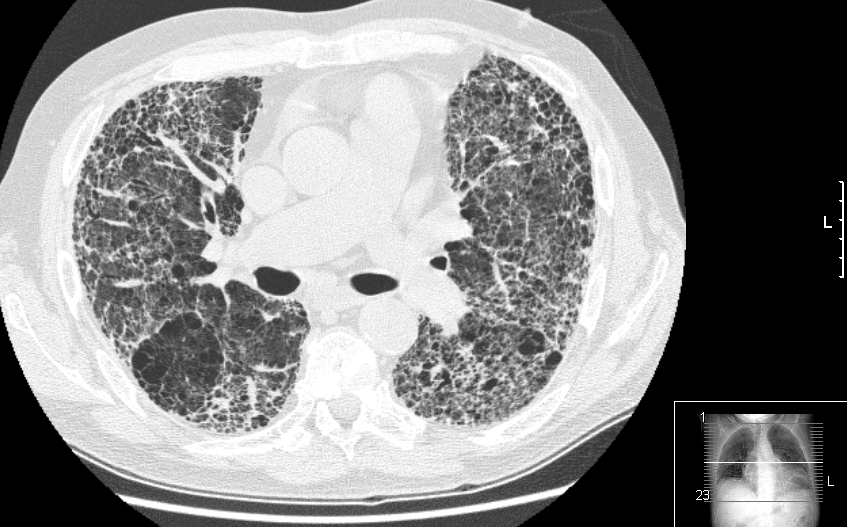

Enfermedad pulmonar intersticial. Revisión

24 abril 2024

La enfermedad pulmonar intersticial típicamente se presenta con disnea de esfuerzo y puede progresar a insuficiencia respiratoria. El tratamiento de primera línea incluye nintedanib o pirfenidona para la fibrosis pulmonar idiopática y micofenolato de mofetilo para la enfermedad pulmonar intersticial (EPI) debida a una enfermedad del tejido conectivo. Se debe considerar el trasplante de pulmón en pacientes con EPI avanzada. En pacientes con EPI, el entrenamiento físico mejora la distancia de la prueba de caminata de 6 minutos y la calidad de vida. JAMA.  22 de abril de 2024